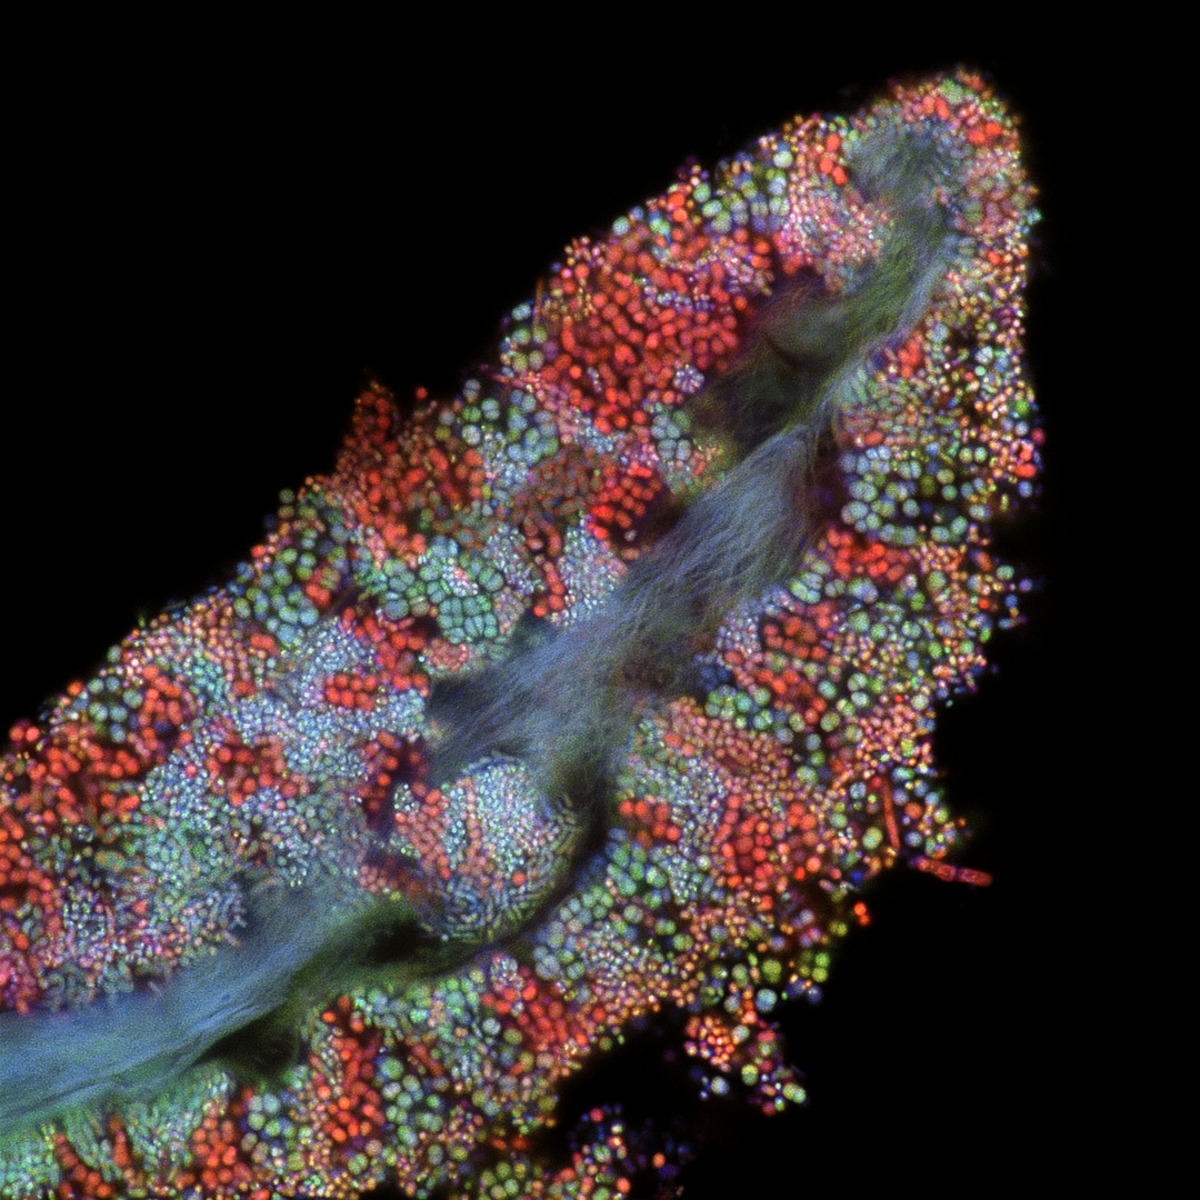

5. Εντερικές λάχνες

Θυμίζει κόσμημα αλλά είναι κάτι τελείως διαφορετικό! Είναι εντερικές λάχνες, δηλαδή μικροσκοπικές προεξοχές που αποτελούνται από κύτταρα και διατρέχουν όλο το μήκος του λεπτού εντέρου. Η εικόνα ανήκει στη Δρ. Amy C. Engevik.